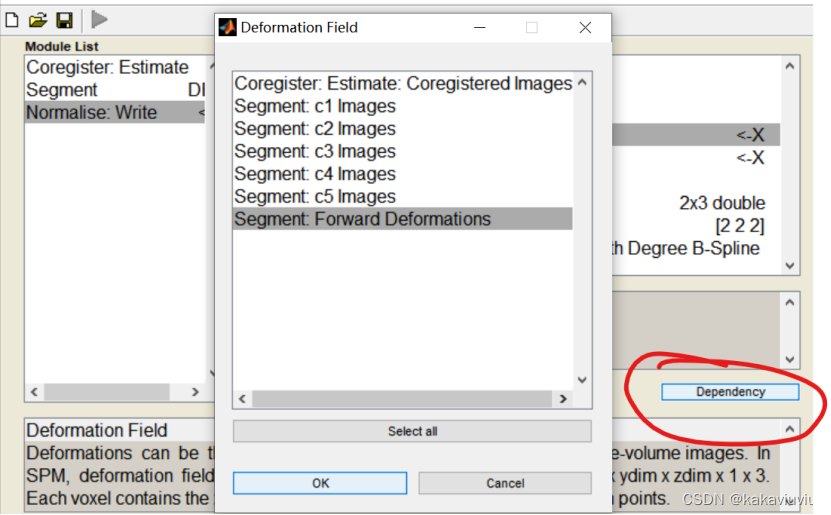

3.个体fMRI---应用第二步的形变场--->标准空间fMRI(Normaliz&Write)

再选择normalise

点dependency